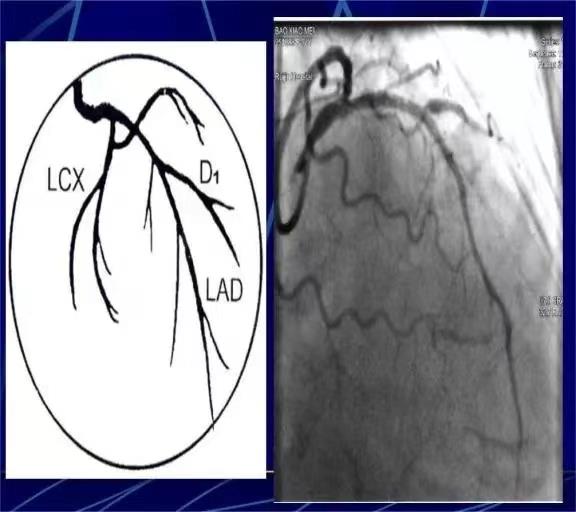

心脏冠脉造影

脑动脉造影

同一名患者既出现了冠脉的严重狭窄(左图),又出现了颈动脉的严重狭窄(右图)。